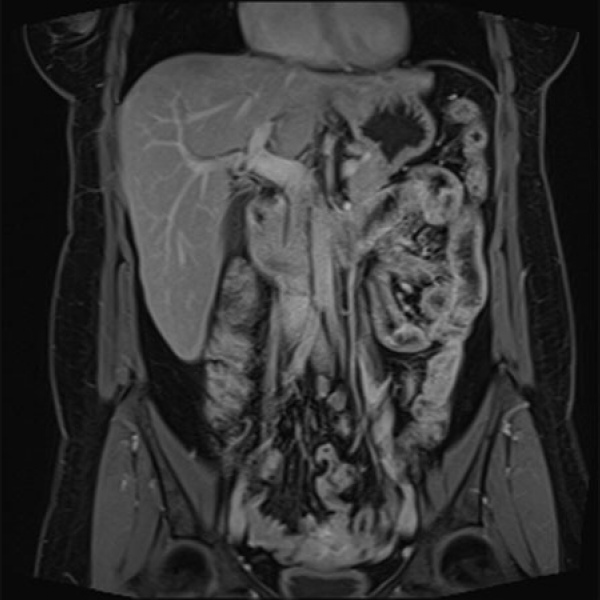

Resonancia nuclear magnetica de abdomen contrastado. EN. Codigo 883401C (2022)

ESCANOGRAFIA NEUROLOGICA S.A.

Medellin, Barrio Prado Centro: Calle 59 # 50 A - 14

Sabaneta, Carrera 48 # 50 sur 128. Al interior del Centro Comercial Mayorca Mega Plaza